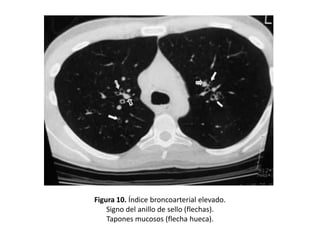

Criterios diagnósticos de

bronquiectasias por TAC

• El signo fundamental es la demostración de la

dilatación bronquial tomando como patrón de

referencia el diámetro de la arteria bronquial

adyacente.

• En condiciones normales los diámetros del

bronquio y del vaso acompañante son

similares.

Signos directos

• Dilatación bronquial:

– Presencia de un diámetro bronquial interno mayor

que el de la arteria bronquial adyacente. (Índice

broncoarterial)

– En el caso de las BQ es, por lo tanto, mayor de 1.

• Cuando el bronquio transcurre perpendicular al

plano de sección, esta dilatación da lugar al

“signo del anillo de sello”:

– El bronquio dilatado forma un anillo y la arteria

acompañante, el sello. (Figura 10)

Figura 10. Índice broncoarterial elevado.

Signo del anillo de sello (flechas).

Tapones mucosos (flecha hueca).